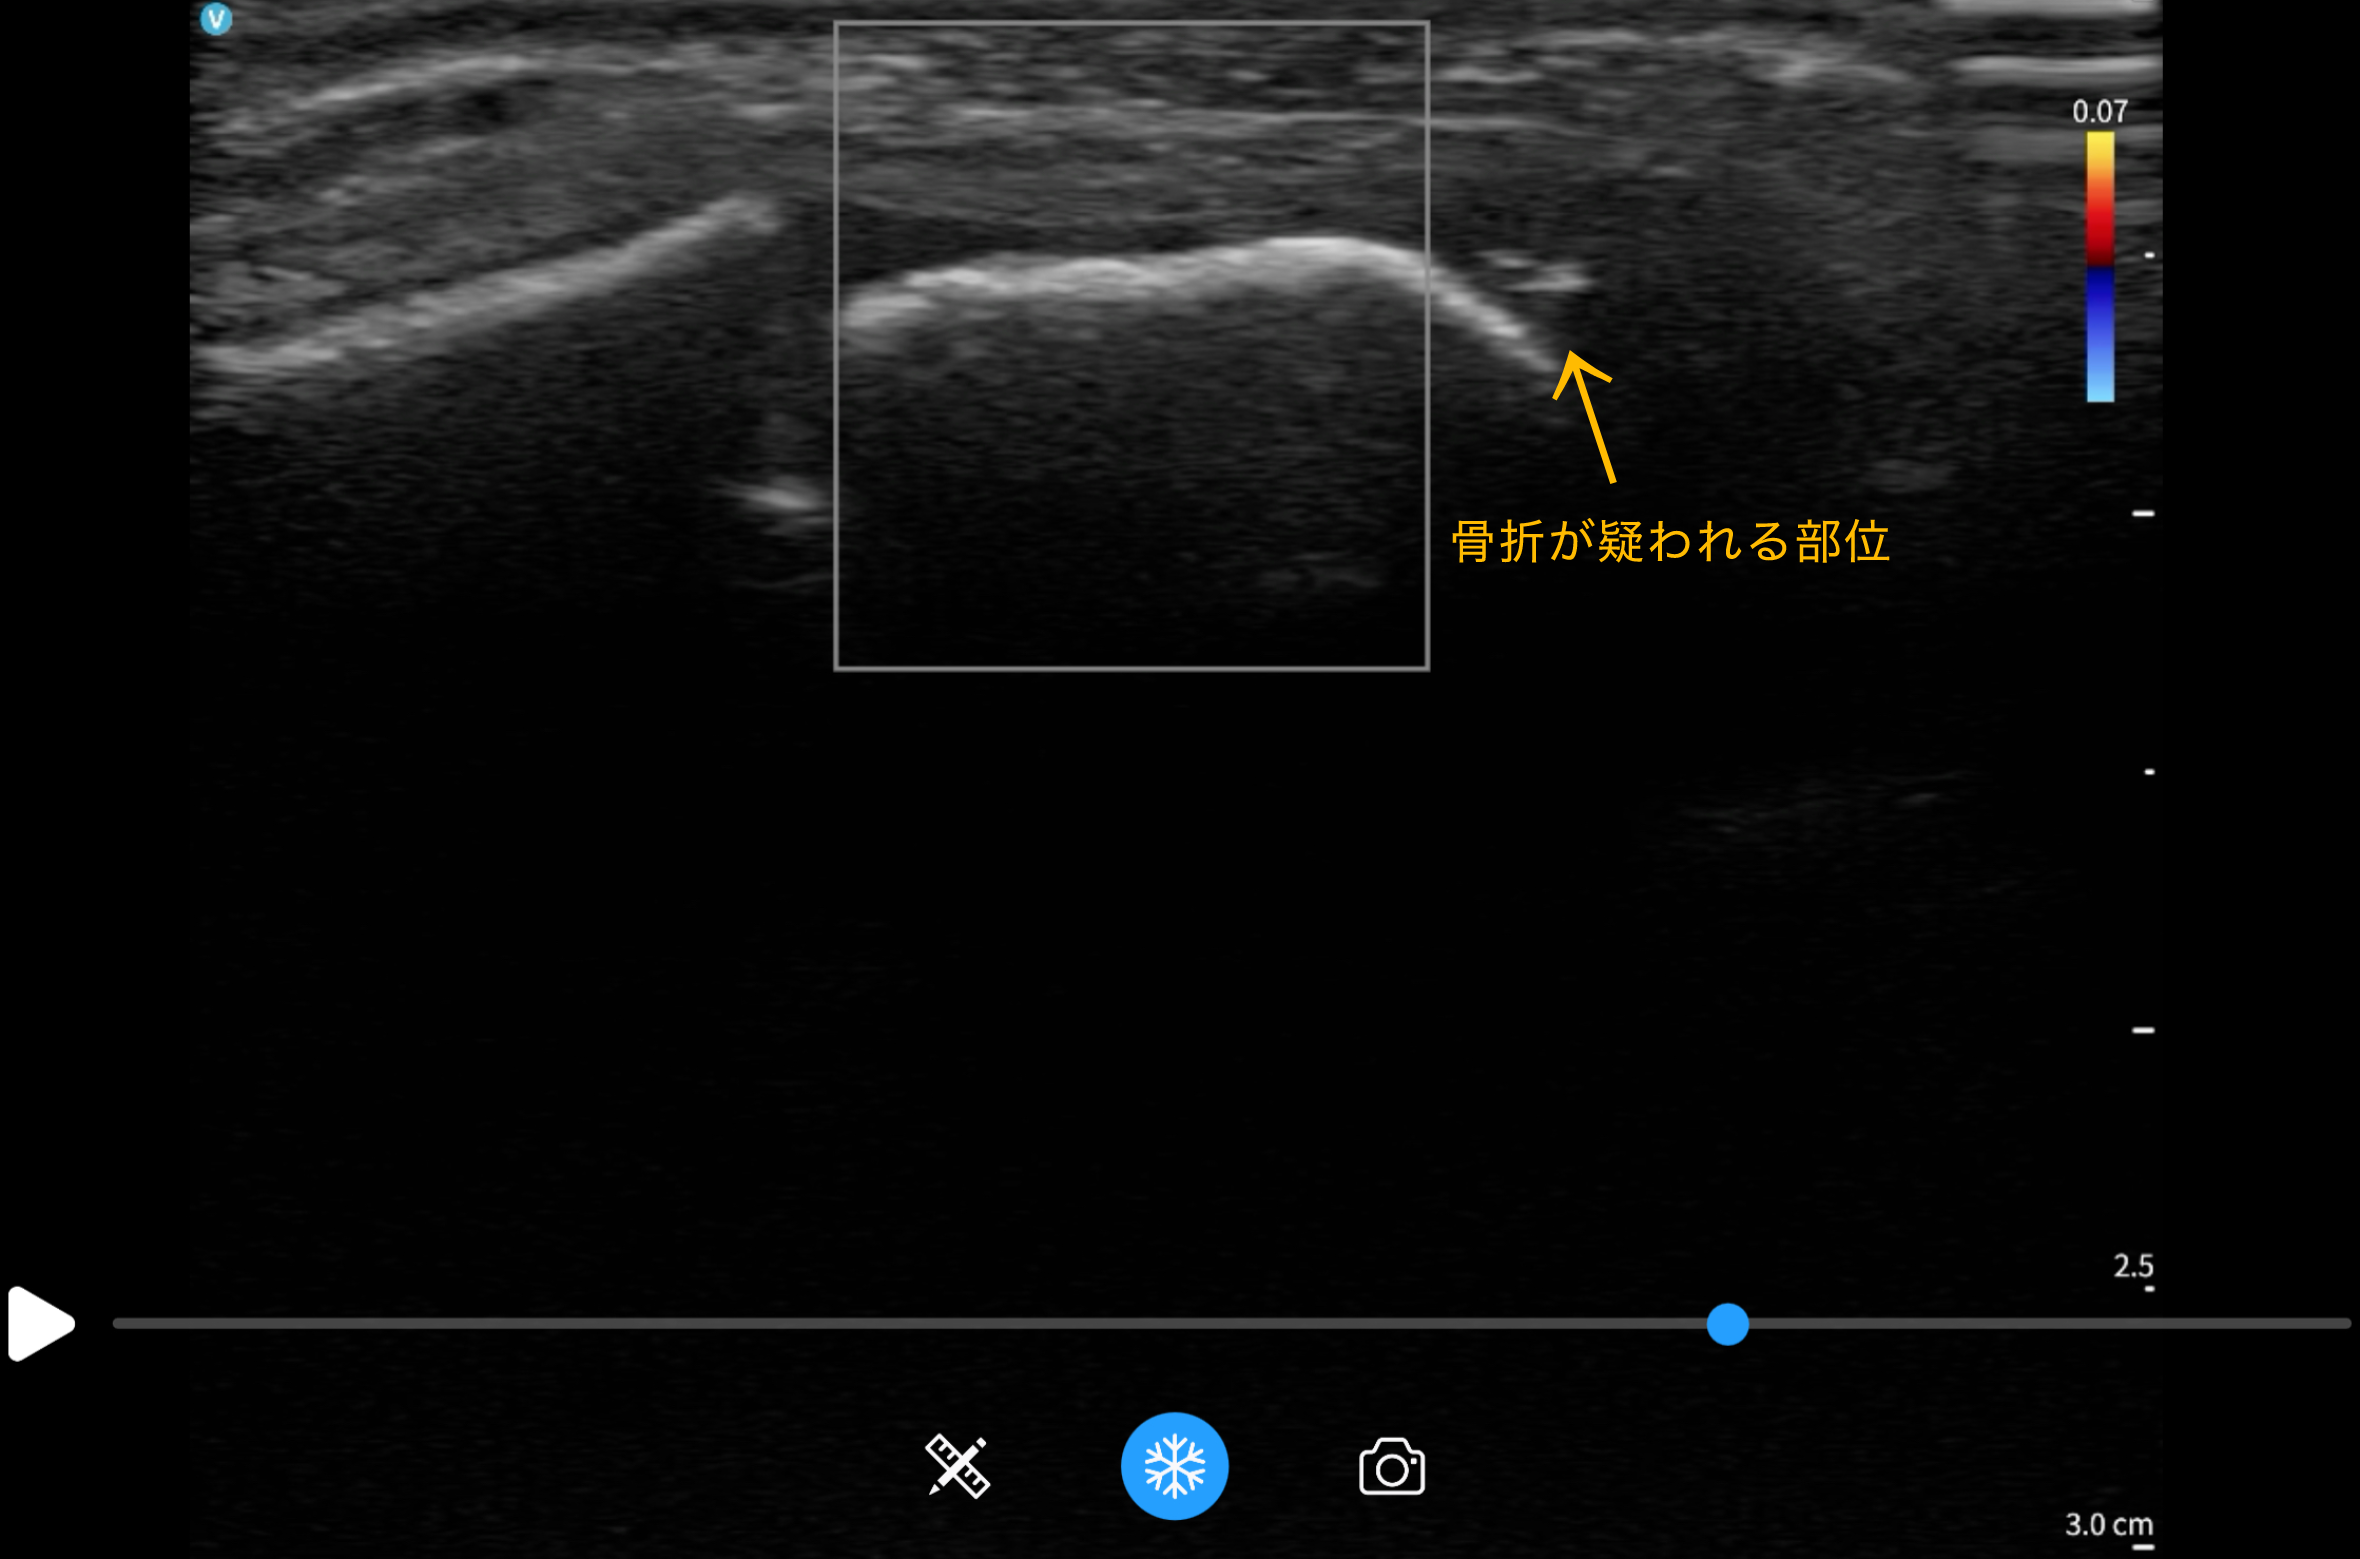

エコー画像で確認したところ、腓骨の下端部分に骨の連続性が乱れている部分が確認されました。

また、提携している整形外科に紹介したところ、X線検査により「足関節外果骨折(前距腓裂離骨折)」と診断されました。